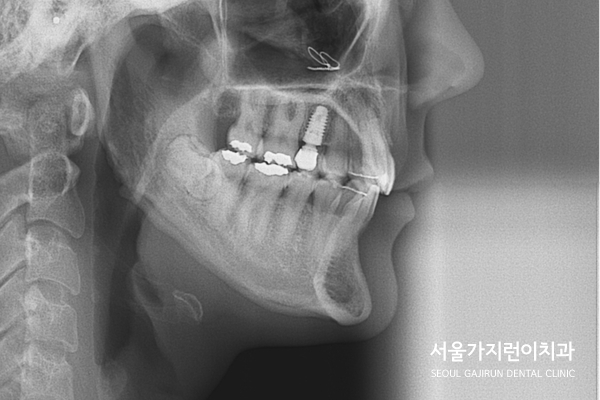

그래서 상기 환자의 경우 상악 전치의 전돌을 해소하기 위해

미니스크류를 사용한 치아교정이 이루어졌는데요.

설측탄댐방식을 이용해 치아이동에 필요한 힘을 충분히 줄 수 있었습니다.

교정을 고려할 때는 임플란트 및 보철치료도 함께 염두해야 하는데요.

상기 환자분의 경우 임플란트 치아가 움직이지 않도록 최대한 노력하였으며

다행히도 임플란트 이상 없이 교정력을 유지하면서 치아교정을 마무리할 수 있었습니다.